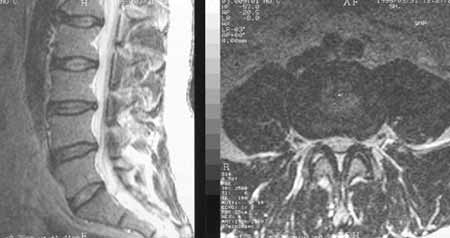

Рис. 1. Диффузная протрузия межпозвонкового диска L3-L4, больше выраженная слева. Узкий позвоночный канал. Сагитальное и аксиальное изображения.